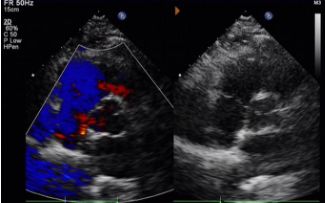

Tag 1 bis 9 Monate:

Kein Rest-Shunt beobachtet.

Allmähliche Verringerung der Geräte echogenität.